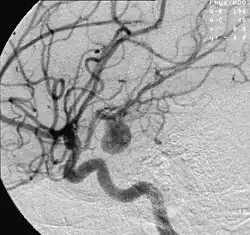

Angiografía de un aneurisma en una arteria cerebral. | ||

Un aneurisma es una pequeña protuberancia con forma de globo y llena de sangre que se forma en las paredes de los vasos sanguíneos.[1] Cualquier vaso puede presentarlo pero es más común en la arteria aorta, los vasos cerebrales, la arteria poplítea, la arteria mesentérica y la arteria esplénica.[2]

Un aneurisma cerebral puede ocurrir en venas o arterias de la base del cerebro (en el polígono de Willis) y un aneurisma aórtico ocurre en la arteria principal que lleva sangre desde el ventrículo izquierdo del corazón al cerebro. Cuando el tamaño de un aneurisma aumenta, hay un riesgo significativo de rotura, lo que puede resultar en hemorragias graves, otras complicaciones o muerte. Los aneurismas pueden ser hereditarios o causados por enfermedades que debilitan las paredes de los vasos sanguíneos.

Los aneurismas cerebrales, también conocidos como aneurismas intracraneales o del cerebro, se presentan más comúnmente en la arteria cerebral anterior, que es parte del círculo de Willis. Los siguientes sitios más comunes de la aparición aneurisma cerebral se encuentran en la arteria carótida interna.[5]

El diagnóstico de un aneurisma cerebral roto se hace comúnmente mediante la búsqueda de signos de hemorragia subaracnoidea en la tomografía computarizada (TC). Si la TC es negativa, pero una ruptura de aneurisma se sigue sospechando basada en los hallazgos clínicos, una punción lumbar se puede realizar para detectar sangre en el líquido cefalorraquídeo. La tomografía computada (CTA) es una alternativa a la angiografía tradicional, y se puede realizar sin la necesidad de un cateterismo arterial. Esta prueba combina un TC convencional con un medio de contraste el cual es inyectado a una vena. Una vez que el medio de contraste se inyecta en una vena, este viaja a las arterias cerebrales, y las imágenes se crean mediante una tomografía computarizada. Estas imágenes muestran exactamente cómo fluye la sangre hacia las arterias cerebrales.